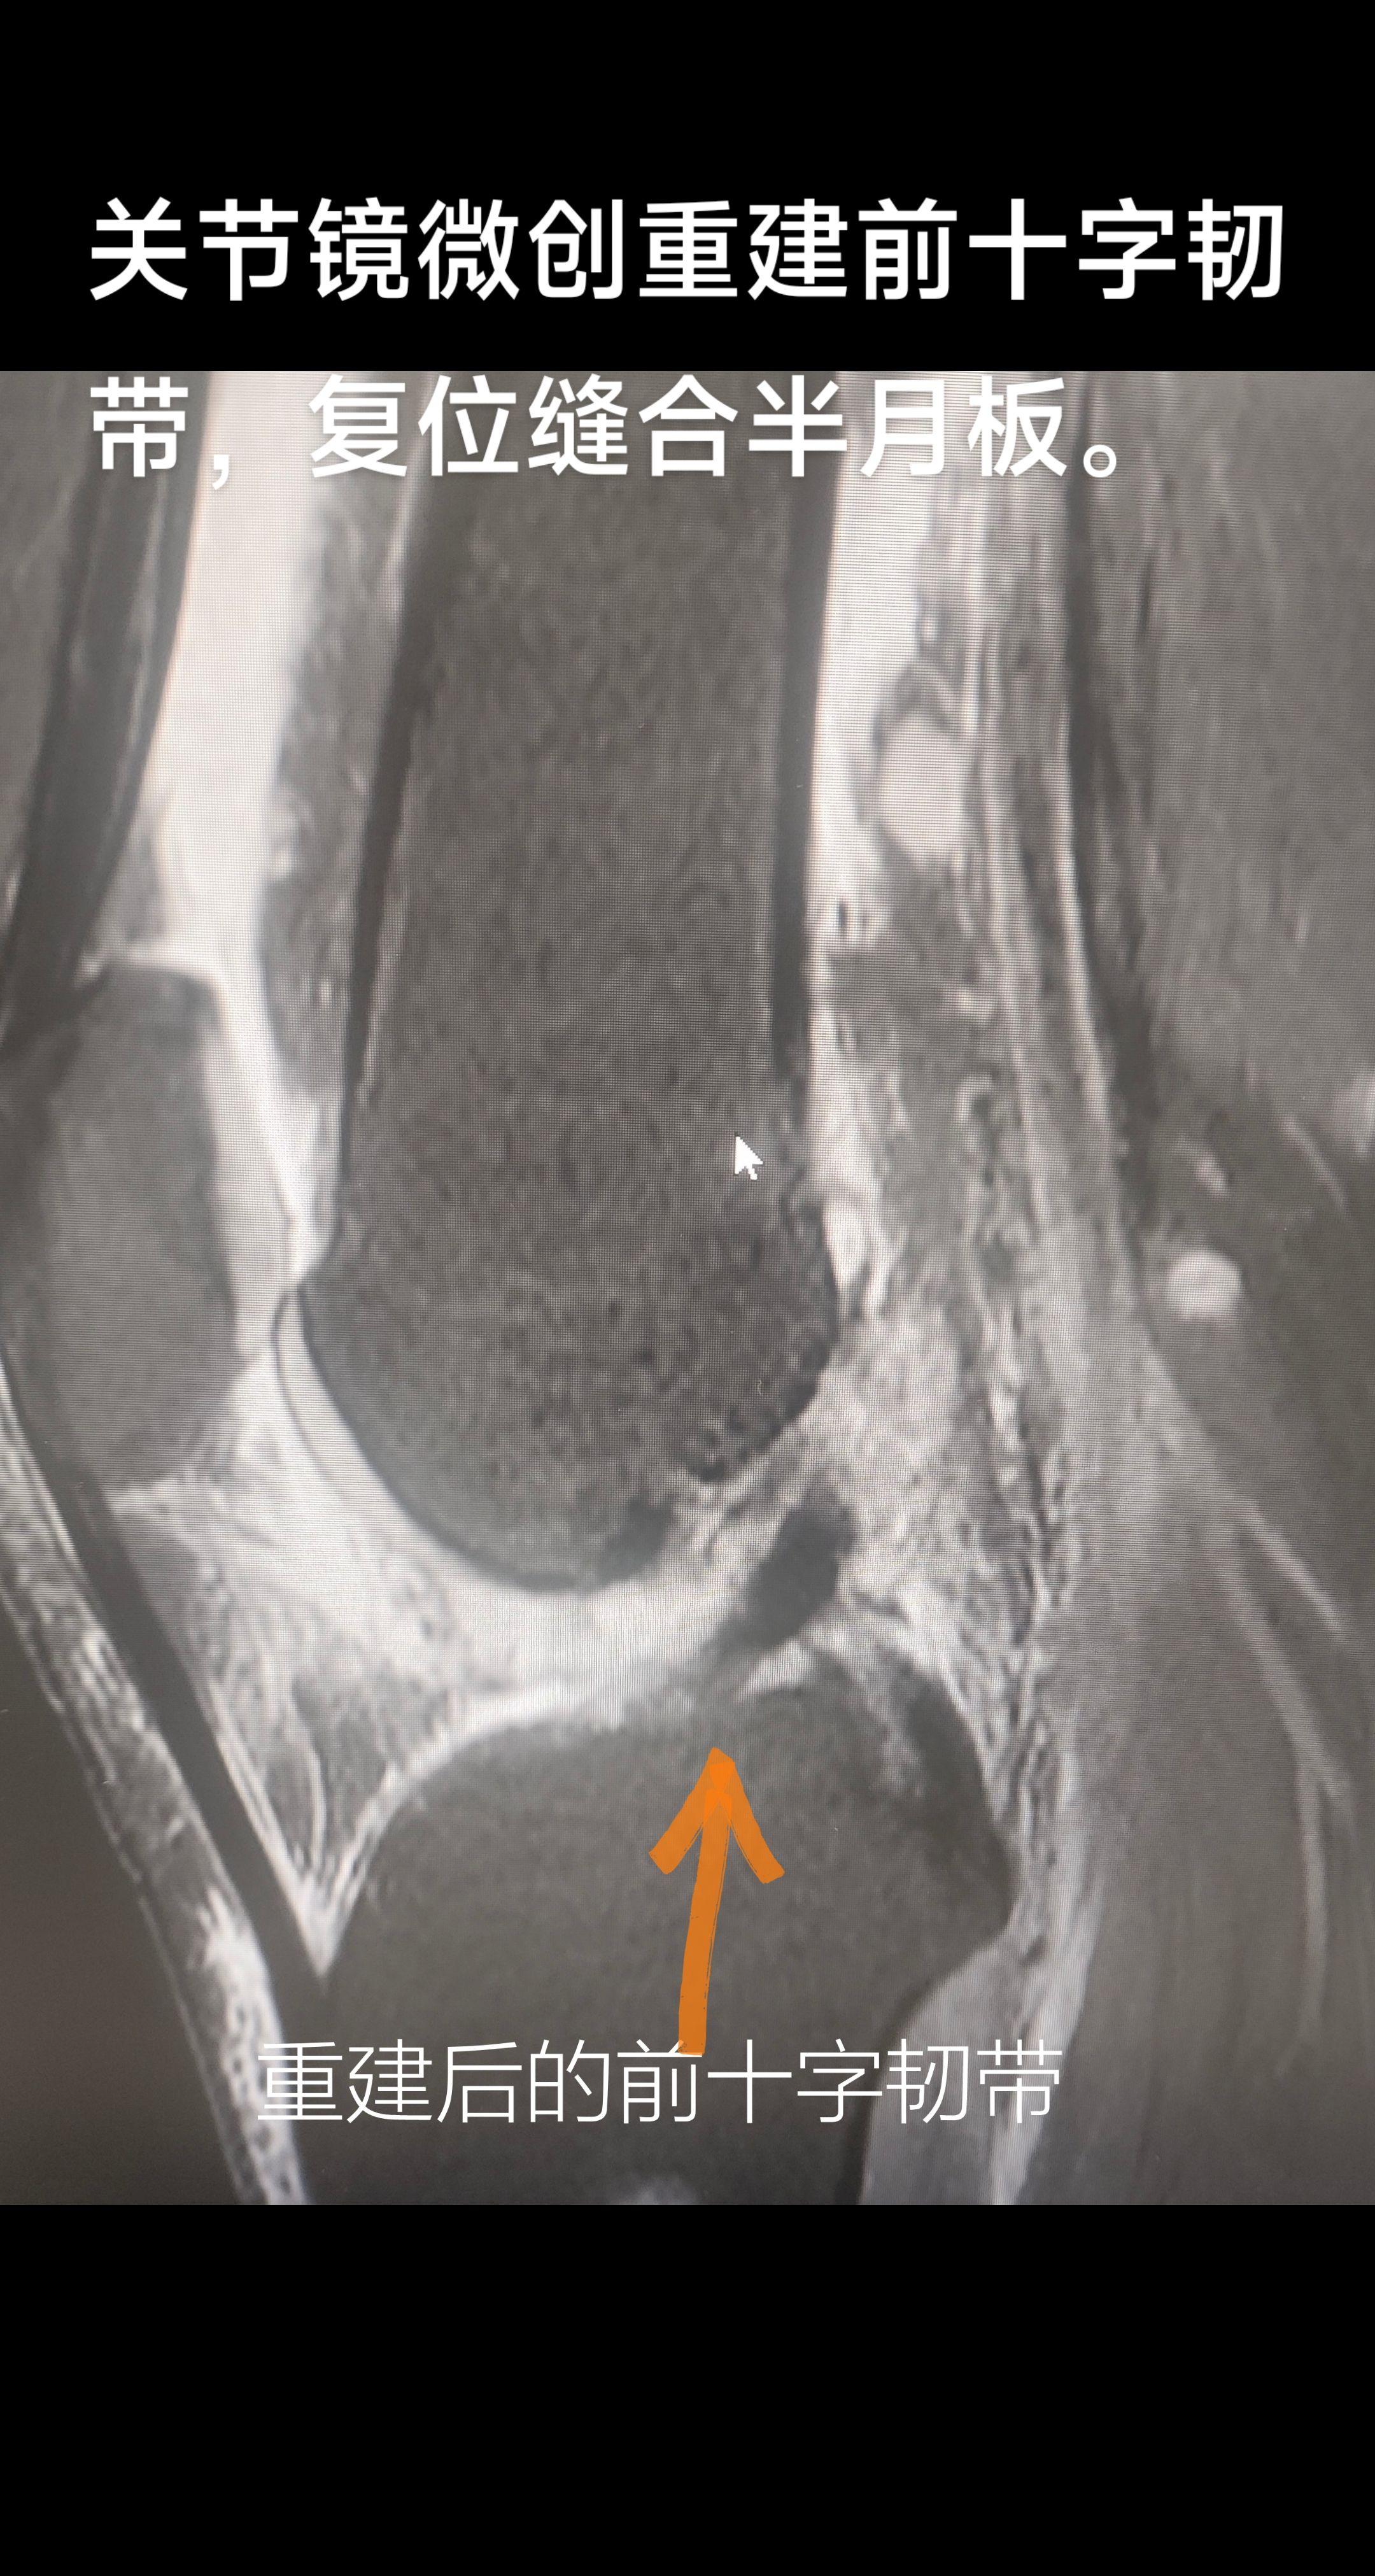

膝关节前十字韧带重建+半月板缝合。